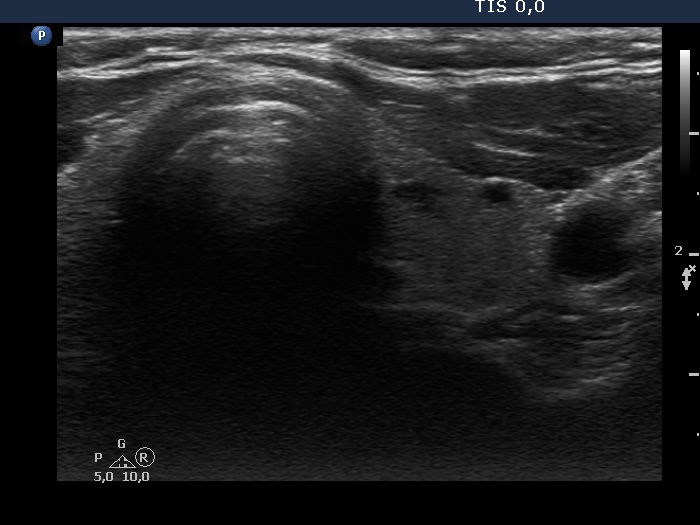

Clinical presentation: A 58-year-old woman was referred for evaluation of a nodular goiter which was discovered on ultrasound screening.

Ultrasonography. The thyroid was echonormal. Beside tiny hypoechoic areas, two larger lesions were found in the right lobe, a moderately hypoechoic and a cystic one.

Cytology of the moderately hypoechoic lesion resulted in benign cystic-colloid goiter.